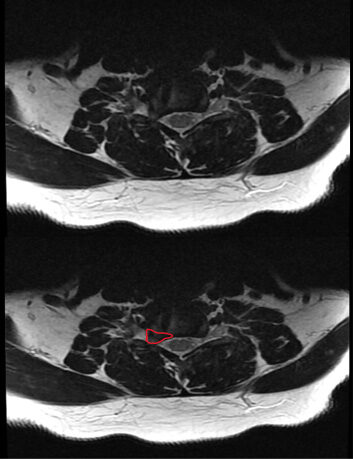

MRI with foraminal stenosis. The disk herniation is outlined in red. It does not cause any stenosis of the spinal cord, but it does cause compression of the nerve roots (yellow) as they exit the spinal canal.

MRI showing cervical disk herniation

pressing on a nerve root (outlined in red on

right picture)